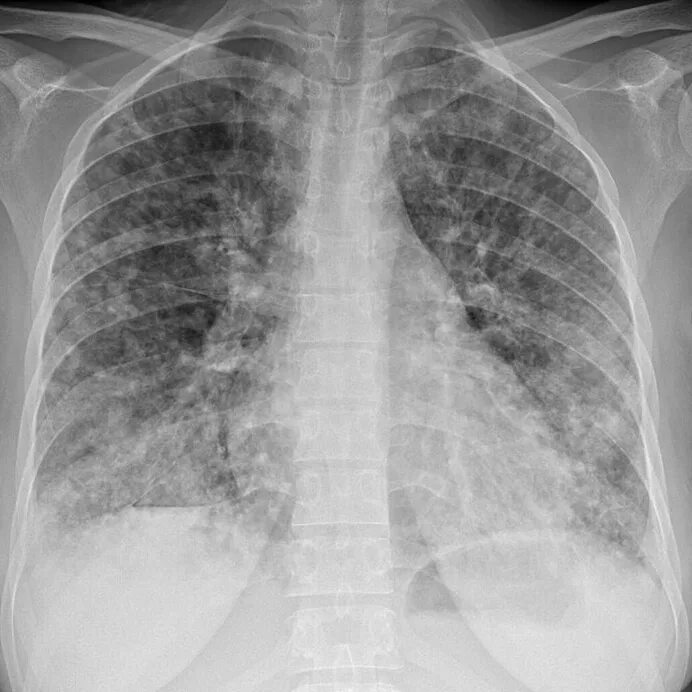

Метастазы в средостении легких